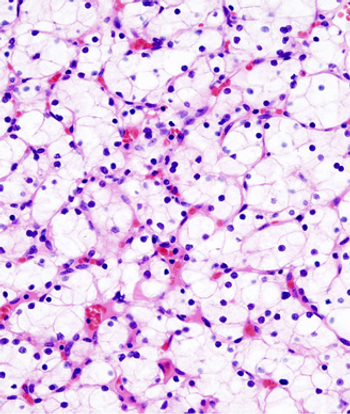

New research shows that tumors found in obese patients may be more indolent than those in nonobese patients, and this may, in part, be related to alterations in fatty acid metabolism explaining the obesity paradox in clear-cell renal cell carcinoma.